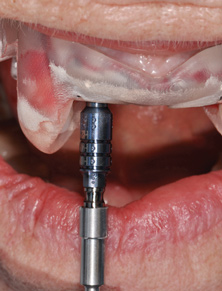

Fig 14. Printed static guide used to precisely control preparation of osteotomy (Fig 14) and delivery of the implant through the guide (Fig 15).

Figure 14

Fig 15. Printed static guide used to precisely control preparation of osteotomy (Fig 14) and delivery of the implant through the guide (Fig 15).

Figure 15

From the data and collaboration in steps 1 through 3, surgical guides can be fabricated for static surgery, and when indicated, prosthetic components, such as custom healing abutments, provisional crowns, or fixed partial dentures, can be produced for delivery at the time of surgery to guide soft-tissue healing. The static approach, better known as computer-guided surgery, refers to the use of tissue-tooth or soft- and hard-tissue-supported surgical templates. In essence, the virtual implant position planned from the CBCT, IOS, and face-in data sets is reproduced. The guide is produced with master cylinders (portals) through which the osteotomy preparation drills are introduced, and in full-guidance cases, the delivery of the implant is carried out (Figure 14 and Figure 15). Dynamic guided surgery or computer "navigation" traces the virtual implant position directly from CBCT data and employs motion tracking or real-time tracking technology to prepare the implant osteotomy. This makes it possible to determine the actual position of the surgical drill on the reconstructed 3D image provided by the CBCT. The surgeon is guided to the position that was planned preoperatively while he or she performs the surgical procedure. Examples of dynamic navigation systems are Navident (ClaroNav, claronav.com), X-Guide Dynamic 3D Navigation (X-Nav, x-navtech.com), Image Guided Implant (IGI) Dentistry System (Image Navigation, image-navigation.com), Inliant® (Navigate Surgical, navigatesurgical.com), and YOMI®, a robotic haptic guidance system (Neocis, neocis.com).